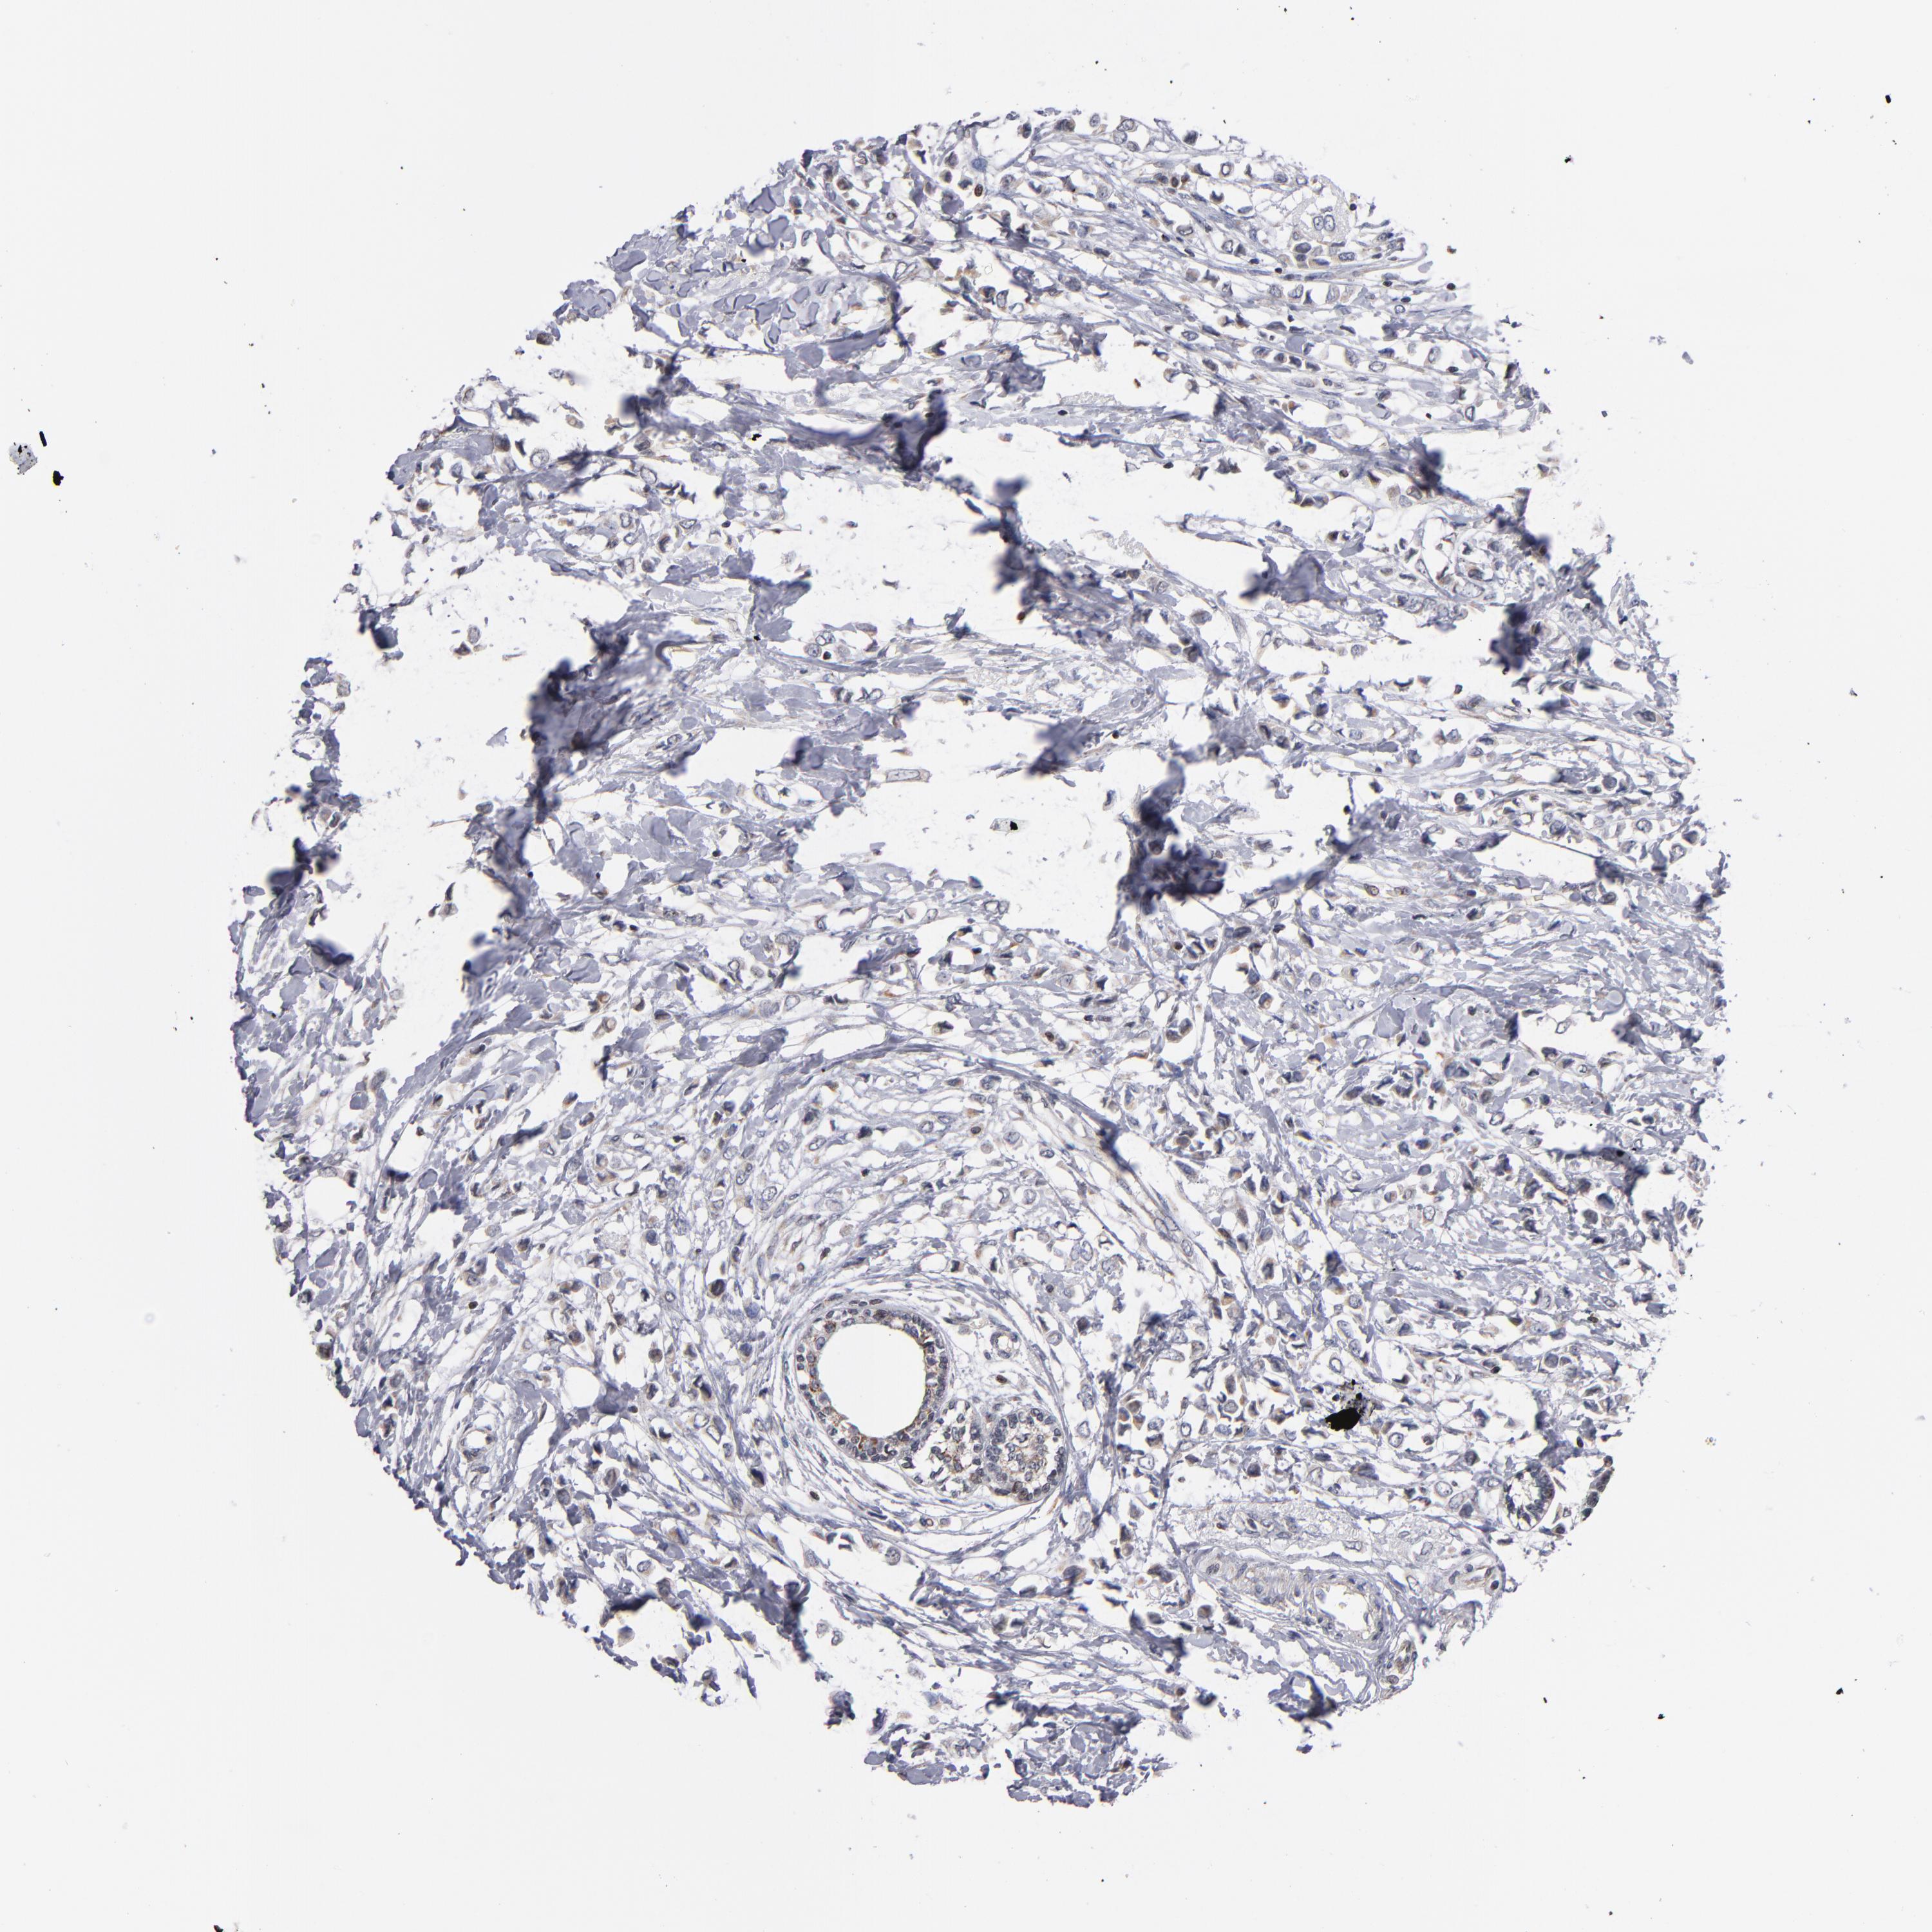

BRCA TCGA BRCA VALIDATION PROTEIN EXPRESSION

ANTIBODIES

AND

VALIDATION